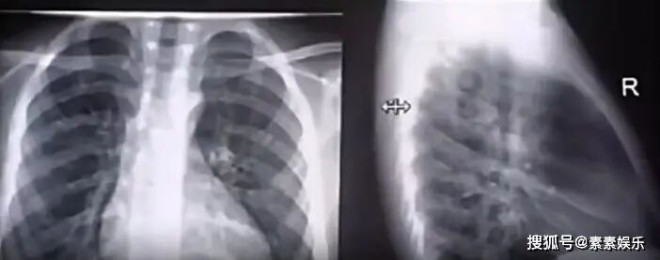

2月3日,韩国KBS节目公开了大S在日本离世的整个细节过程,节目组强调:造成大S心脏骤停的主要原因,还是与当时的旅游有关。 ![]() 节目组深度还原了大S整个离世的时间轴,从25年的1月29日开始,大S和家人从台北飞场飞往日旅行。 抵达不久之后,大S整个人的状态就已经属于感冒期内。 ![]() 据当时日本方面接待他们一家人的导游透露,当时的徐小姐在机场就已经有了高烧的症状,并且她已经伴随有全身酸痛的情况发生。 而大S为了不扫家人的兴,初步判断她只是普通感冒,只要入住酒店之后身体会微微有缓和。 ![]() 抵达酒店之后,家人一起开始泡温泉,而大S也尝试了,并且是在露天的环境之中泡温泉。外热再加上严重的感冒,当时她还伴随着发烧,所以泡温泉这一行为,直接加速了大S的感冒状态恶化。 ![]() 韩国媒体称,泡温泉这个行为,使原本就有心脏疾病的她血管压力上升。当时她的肺部感染也已经开始扩散,两个重要器官的双重伤害之下,这就是她在短时间内心脏发生骤停的原因。 ![]() 另外据透露,当时大S的病情加重时,她其实已经被送到了日本的乡下医院急诊室内。但当时大S强烈希望自己能回家治疗,希望自己能快一点回家。 ![]() 这才有了后面家人陪她一起赶往机场,准备坐飞机返回台北。但就在回家的路上,大S的病情再一次恶化,前往机场的途中心脏已经骤停。 ![]() 救护车又接到她,将她再次运往附近的医院,但很可惜,在经历了长达14小时的心肺复苏,再加上其他的抢救治疗,大S最终仍旧没有恢复意识,因重度肺部感染和心脏器官衰竭离世。 ![]() 从整个抢救治疗与生病前后来看,当时像大S这一种突发情况。如果她在第一次进入医院的时候就选择重视,而不是出院,可能她的病情还有转机。 ![]() 另外具俊晔,还有小S等亲友在身边,也忽略了这一种感冒的严重性。 已经发烧的情况下,并且全身酸痛的时候,就不该去室外再泡温泉。 ![]() ![]() 这一种内热加外热的双重伤害,也许大S在期间甚至还有吃感冒药的可能性。台媒称泡温泉也许是外因,但吃感冒药又泡温泉这就是最致命的存在。 短短几天,大S在异国他乡心脏骤停,整个过程发生得太快。但从韩媒还原的整个过程来看,大S的人生,注定遭此一劫,惋惜,令人痛心! ![]() 2月4日,媒体称具俊晔可能在近期将返回韩国,他将在韩国与家人一起过年。 大S的雕像揭幕仪式完成了他的一个心愿,也算是他完整与大S告别。 ![]() 小S和徐妈感谢具俊晔这一年来的陪伴,他对熙媛的爱是纯粹的,没有任何杂质的。 目前,具俊晔身边有从韩国来的好朋友姜元来,洪禄基陪伴。他们给了好朋友最大的鼓励,具俊晔的心情也好多了。 |